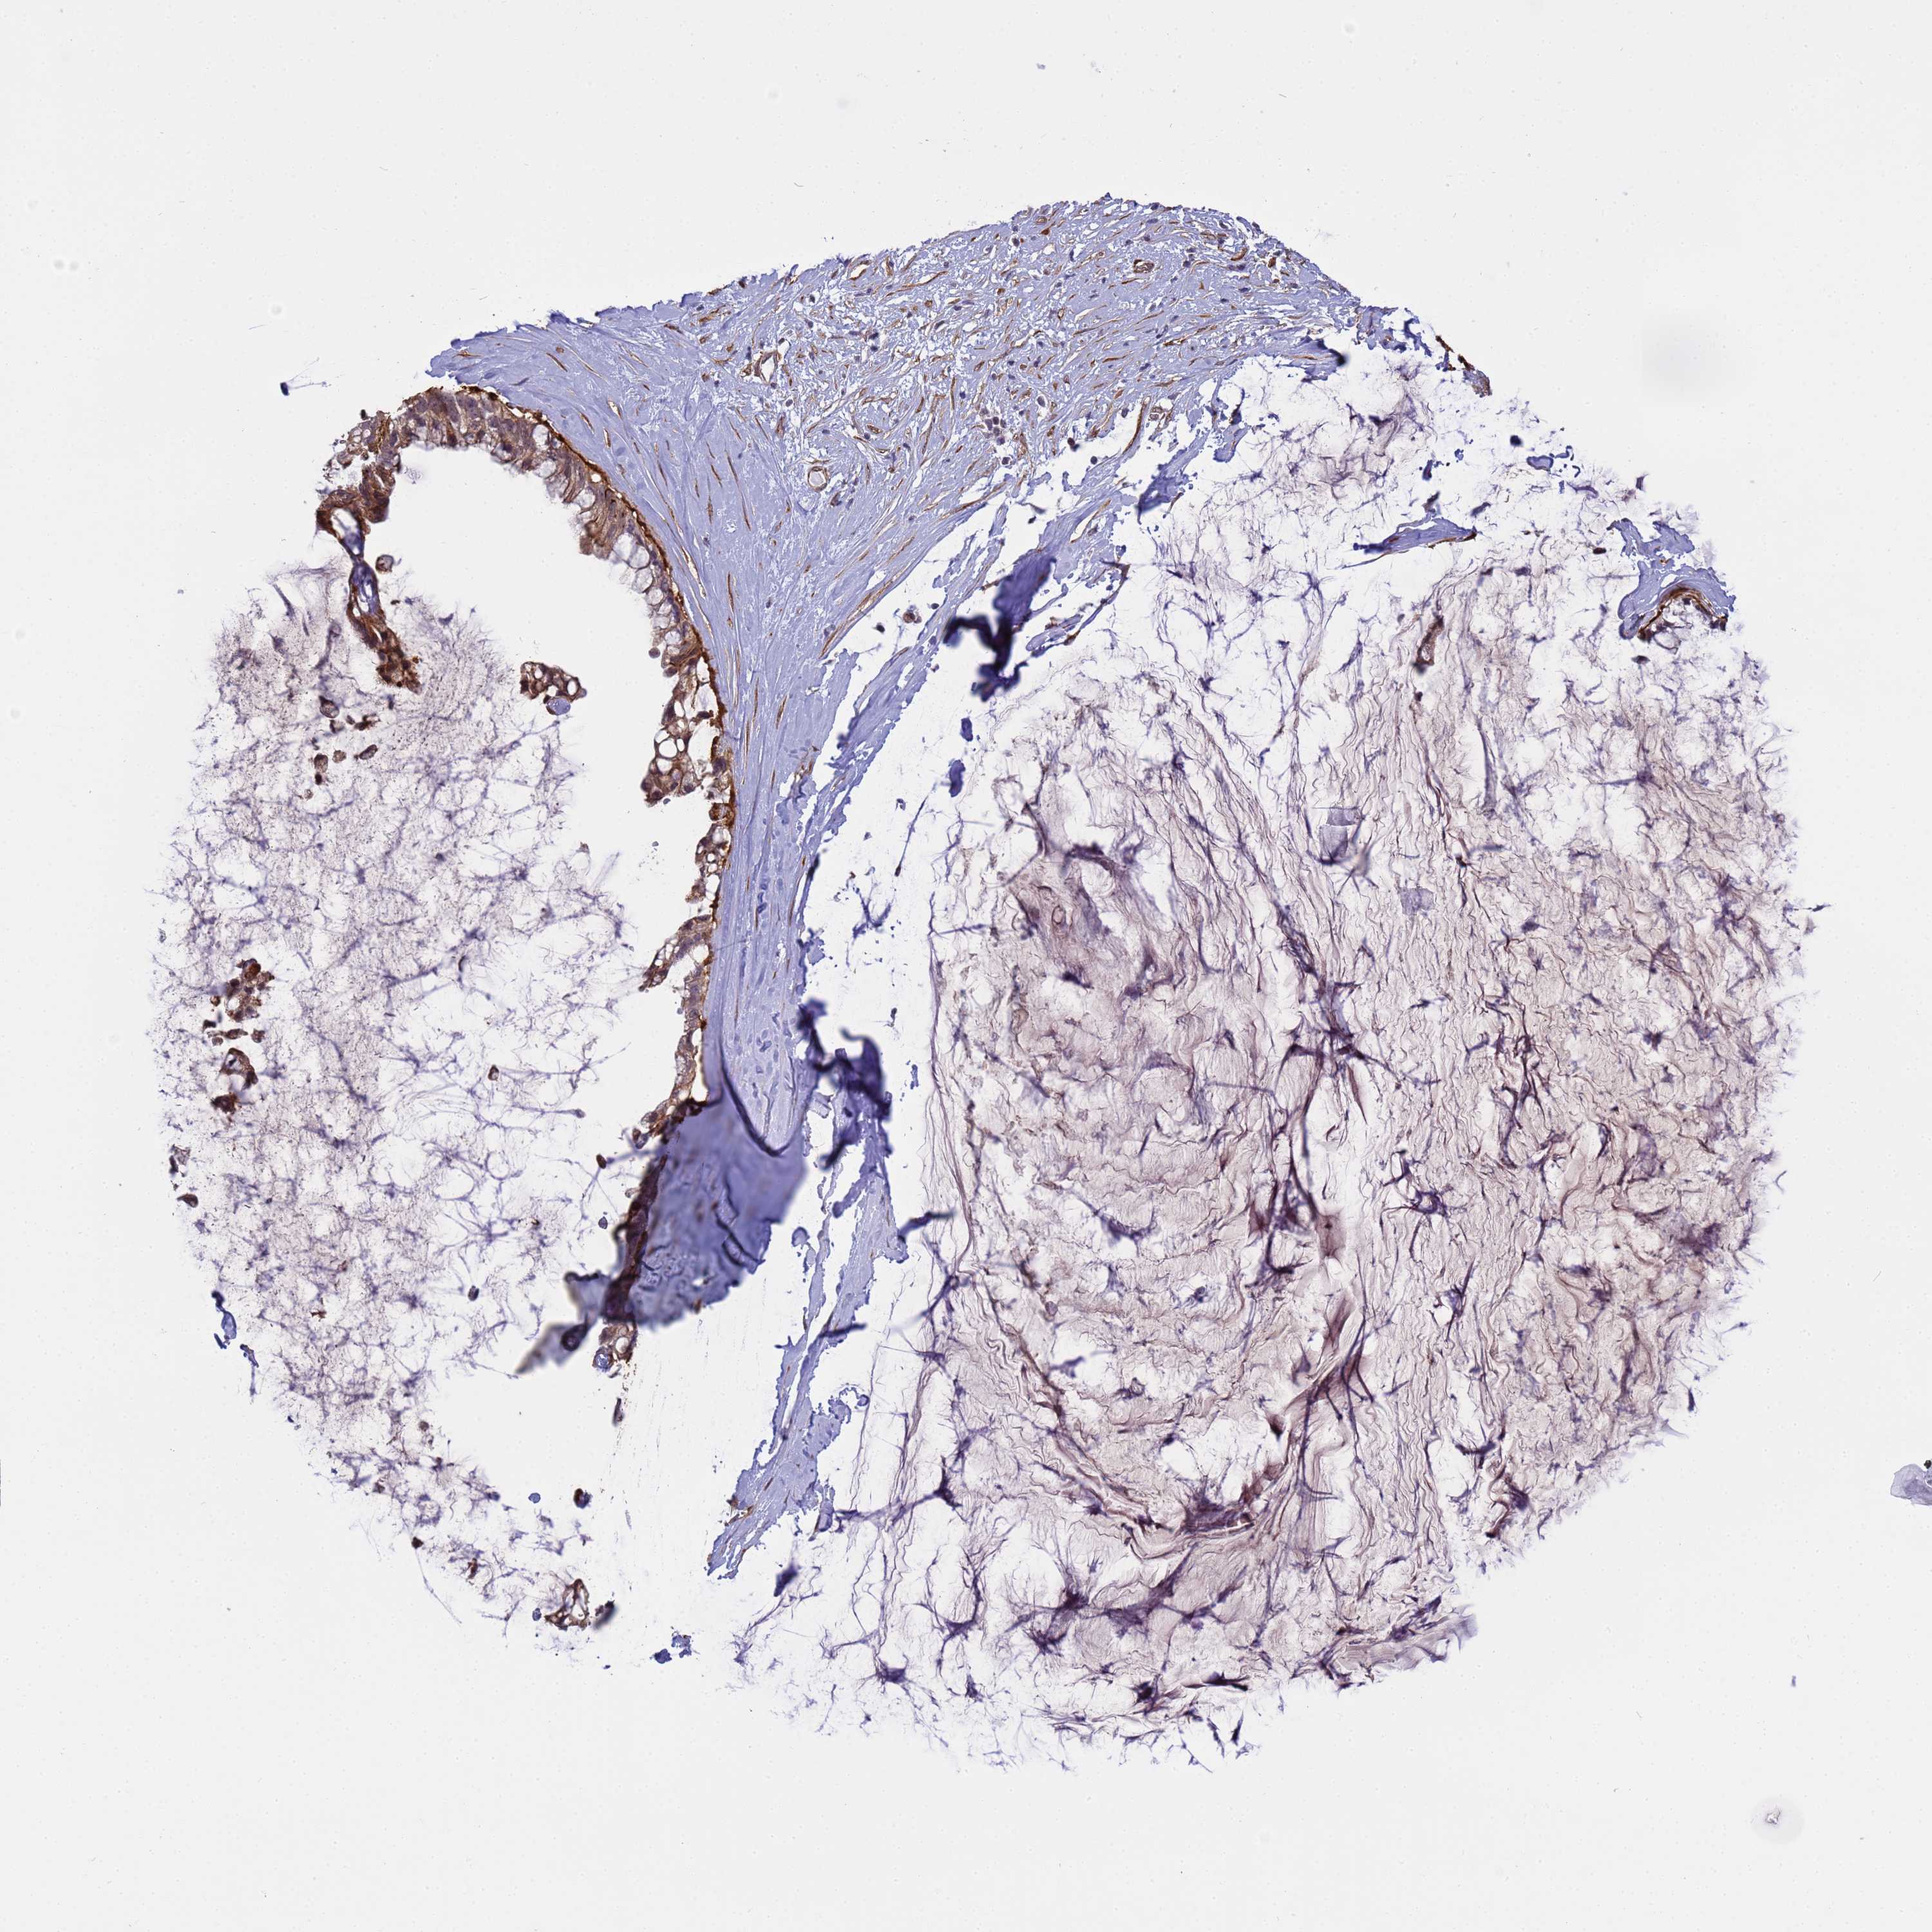

OVARIAN CANCER - Protein expressioni

A mouse-over function shows sample information and annotation data. Click on an image to view it in a full screen mode. Samples can be filtered based on level of antibody staining by selecting one or several of the following categories: high, medium, low and not detected. The assay and annotation is described here.

Note that samples used for immunohistochemistry by the Human Protein Atlas do not correspond to samples in the TCGA dataset.

Antibody stainingi

Antibody staining in the annotated cell types in the current human tissue is reported as not detected, low, medium, or high, based on conventional immunohistochemistry profiling in selected tissues. This score is based on the combination of the staining intensity and fraction of stained cells.

Each image is clickable and will lead to virtual microscopy that enables deeper exploration of all samples and also displays staining intensity scores, fraction scores and subcellular localization as well as patient and tissue information for each sample.

Antibody HPA036348

Antibody HPA036349

Antibody CAB002422

Antibody CAB005258

Cystadenocarcinoma, serous, NOS

Carcinoma, NOS

Cystadenocarcinoma, mucinous, NOS

Carcinoma, endometroid